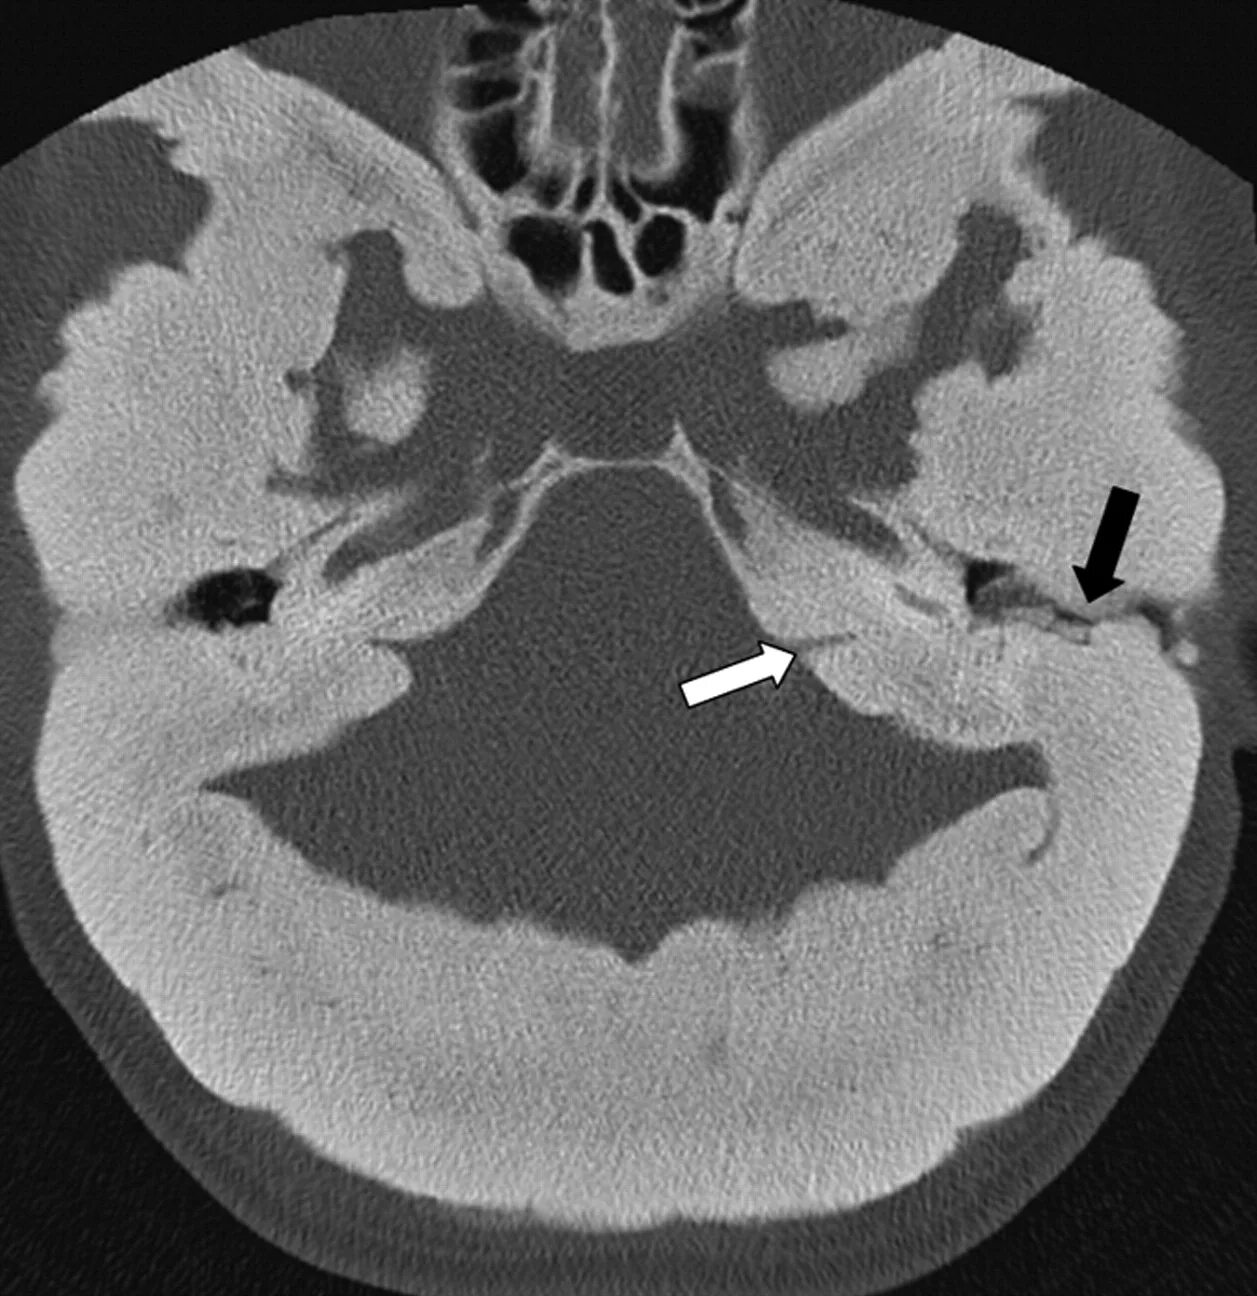

Череп на кт